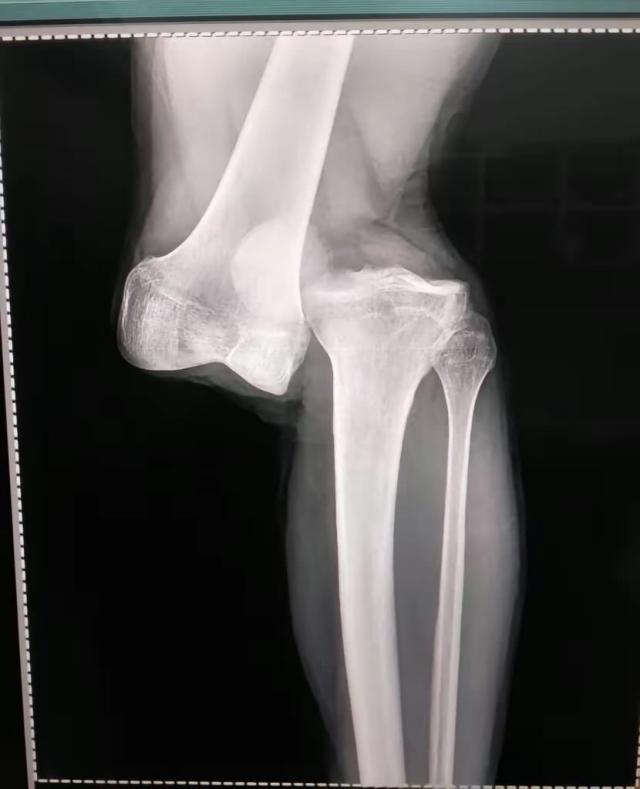

8月2日接受阿根廷一电台采访,阿根廷青年人俱乐部队医亚历杭德罗·隆科罗尼说:“做了23年医生,我从没见过这么严重的伤病。(阿根廷队队医比利尼)干了40年医生,他对我说他也没见过一样的伤病。是膝盖完全脱臼。大腿骨和腓骨基本上分离了。前后十字韧带都撕裂了,我们还得看半月板情况怎样。”

下面是卢西亚诺·桑切斯受伤瞬间照片、在医院病床上拍的腿部照片以及X光检查结果,画面比较强烈,请谨慎考虑是否观看:

X光片